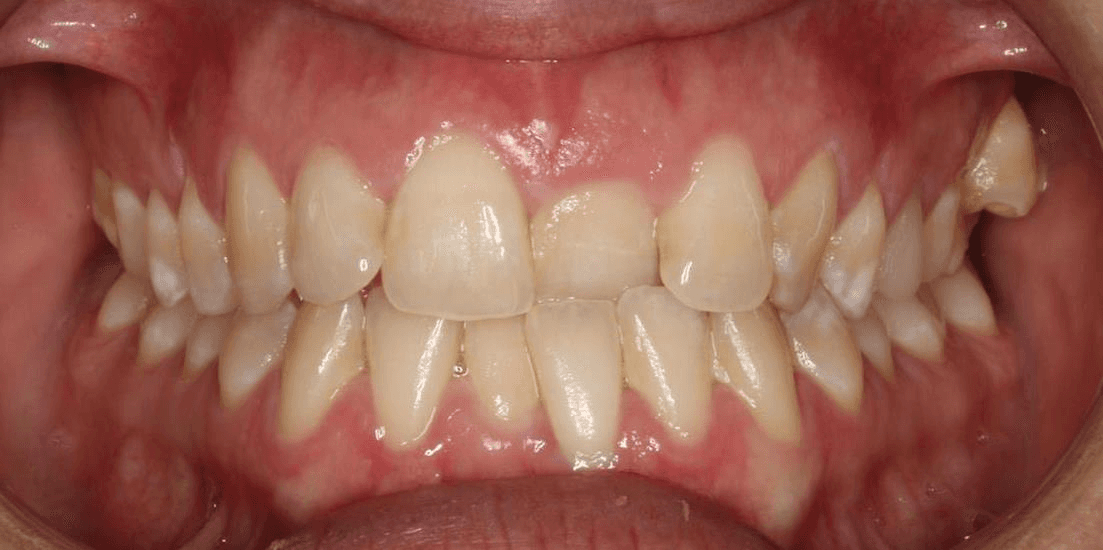

Diganosis: Moderate crowding in both arches, constricted arch forms with anterior and posterior single tooth crossbites, poor smile display

Adjuncts: Occlusal turbos, elastics, attachments, IPR

Initial treatment

INTRAORAL